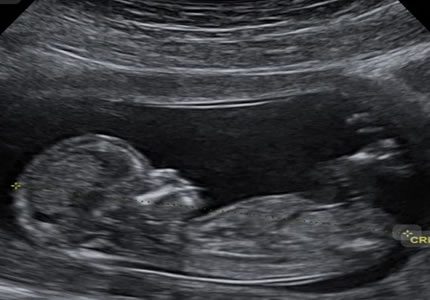

- A thorough "top-to-toe" structural survey of your baby. We systematically evaluate the anatomy—including the brain, spine, heart, and limbs—to screen for developmental markers. This scan offers an in-depth look at your baby's progress during the halfway point of your pregnancy.

- £199